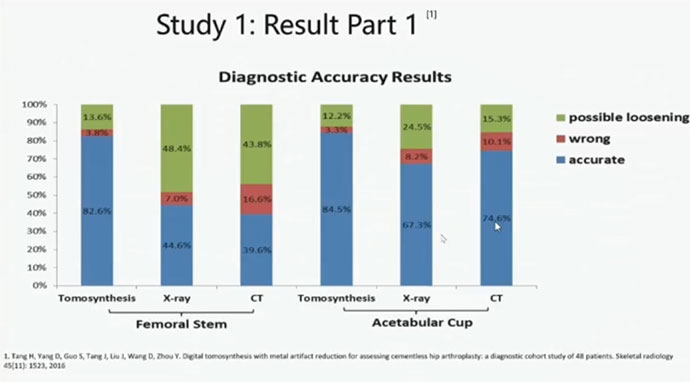

视金识股骨柄以及髋臼侧面的診断精度分别是82.6%和84.5%,比单纯X射线和CT值都高。